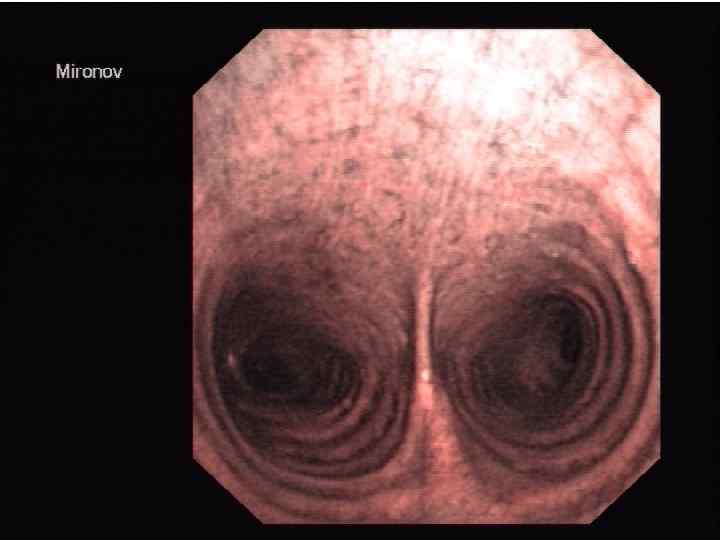

Трахея на нижнем конце делится на 2 ветви, образуя главные бронхи, которые входят в состав корней легких. Главными бронхами начинается бронхиальное дерево. Оно подразделяется на внелегочную и внутрилегочную часть.

Бронхиальное дерево: → долевые → внелегочные зональные бронхи → 10 правый и левый главные бронхи внутрилегочных сегментарных бронхов (бронхи крупного калибра) → субсегментарные бронхиолы (бронхи среднего калибра) → внутридольковые калибра) → междольковые бронхи (бронхи → терминальные бронхиолы малого